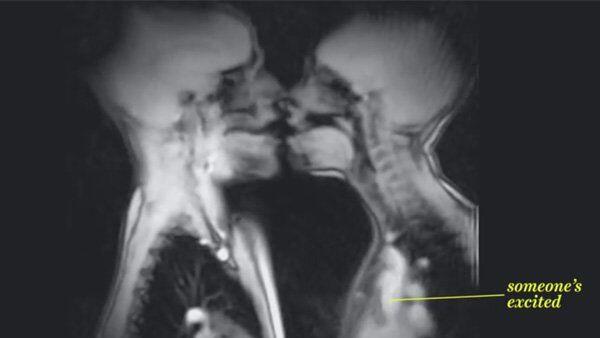

So sieht Sex in einem MRT aus

Ein Youtube-Video zeigt zwei Menschen beim Sex in einem Magnetresonanztomograph (MRT). Die Aufnahmen geben faszinierende Einblicke in den menschlichen Körper.

Alle Fragen, was beim Geschlechtsverkehr genau passiert, beantwortet dieses Video. Vom Zungenkuss, über Geschlechtsverkehr bis hin zur Schwangerschaft. Sogar ein aufgeregt schlagendes Herz bleibt dem MRT nicht vorenthalten. Deutlicher als Ultraschall sind außerdem die Aufnahmen eines ungeborenen Babys.